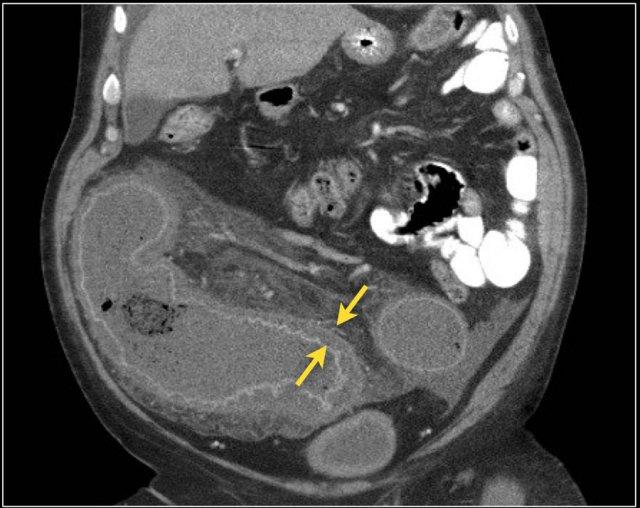

Đây là hình ảnh bệnh nhân thiếu máu cục bộ ruột do huyết khối tĩnh mạch mạc treo tràng trên – SMV (mũi tên đỏ).

Lưu ý tình trạng ứ máu tĩnh mạch trong mạc treo ruột (mũi tên vàng).

Đây là một bệnh nhân khác bị thiếu máu cục bộ một đoạn dài ruột non do tắc ruột quai kín.

Một đặc điểm hình ảnh quan trọng của tắc ruột quai kín là hình ảnh các quai ruột non giãn xếp theo kiểu nan hoa bánh xe với các mạch máu mạc treo hội tụ về một điểm trung tâm.

Các dấu hiệu thiếu máu cục bộ trong tắc ruột quai kín tương tự như ở các bệnh nhân có nguyên nhân thiếu máu cục bộ mạc treo khác:

- Dày thành ruột

- Phù nề mạc treo ruột

- Cổ trướng

- Sự ngấm thuốc của thành ruột trong thiếu máu cục bộ có thể bình thường, tăng do hiện tượng tái tưới máu, hoặc giảm/mất ngấm thuốc như trong trường hợp này.